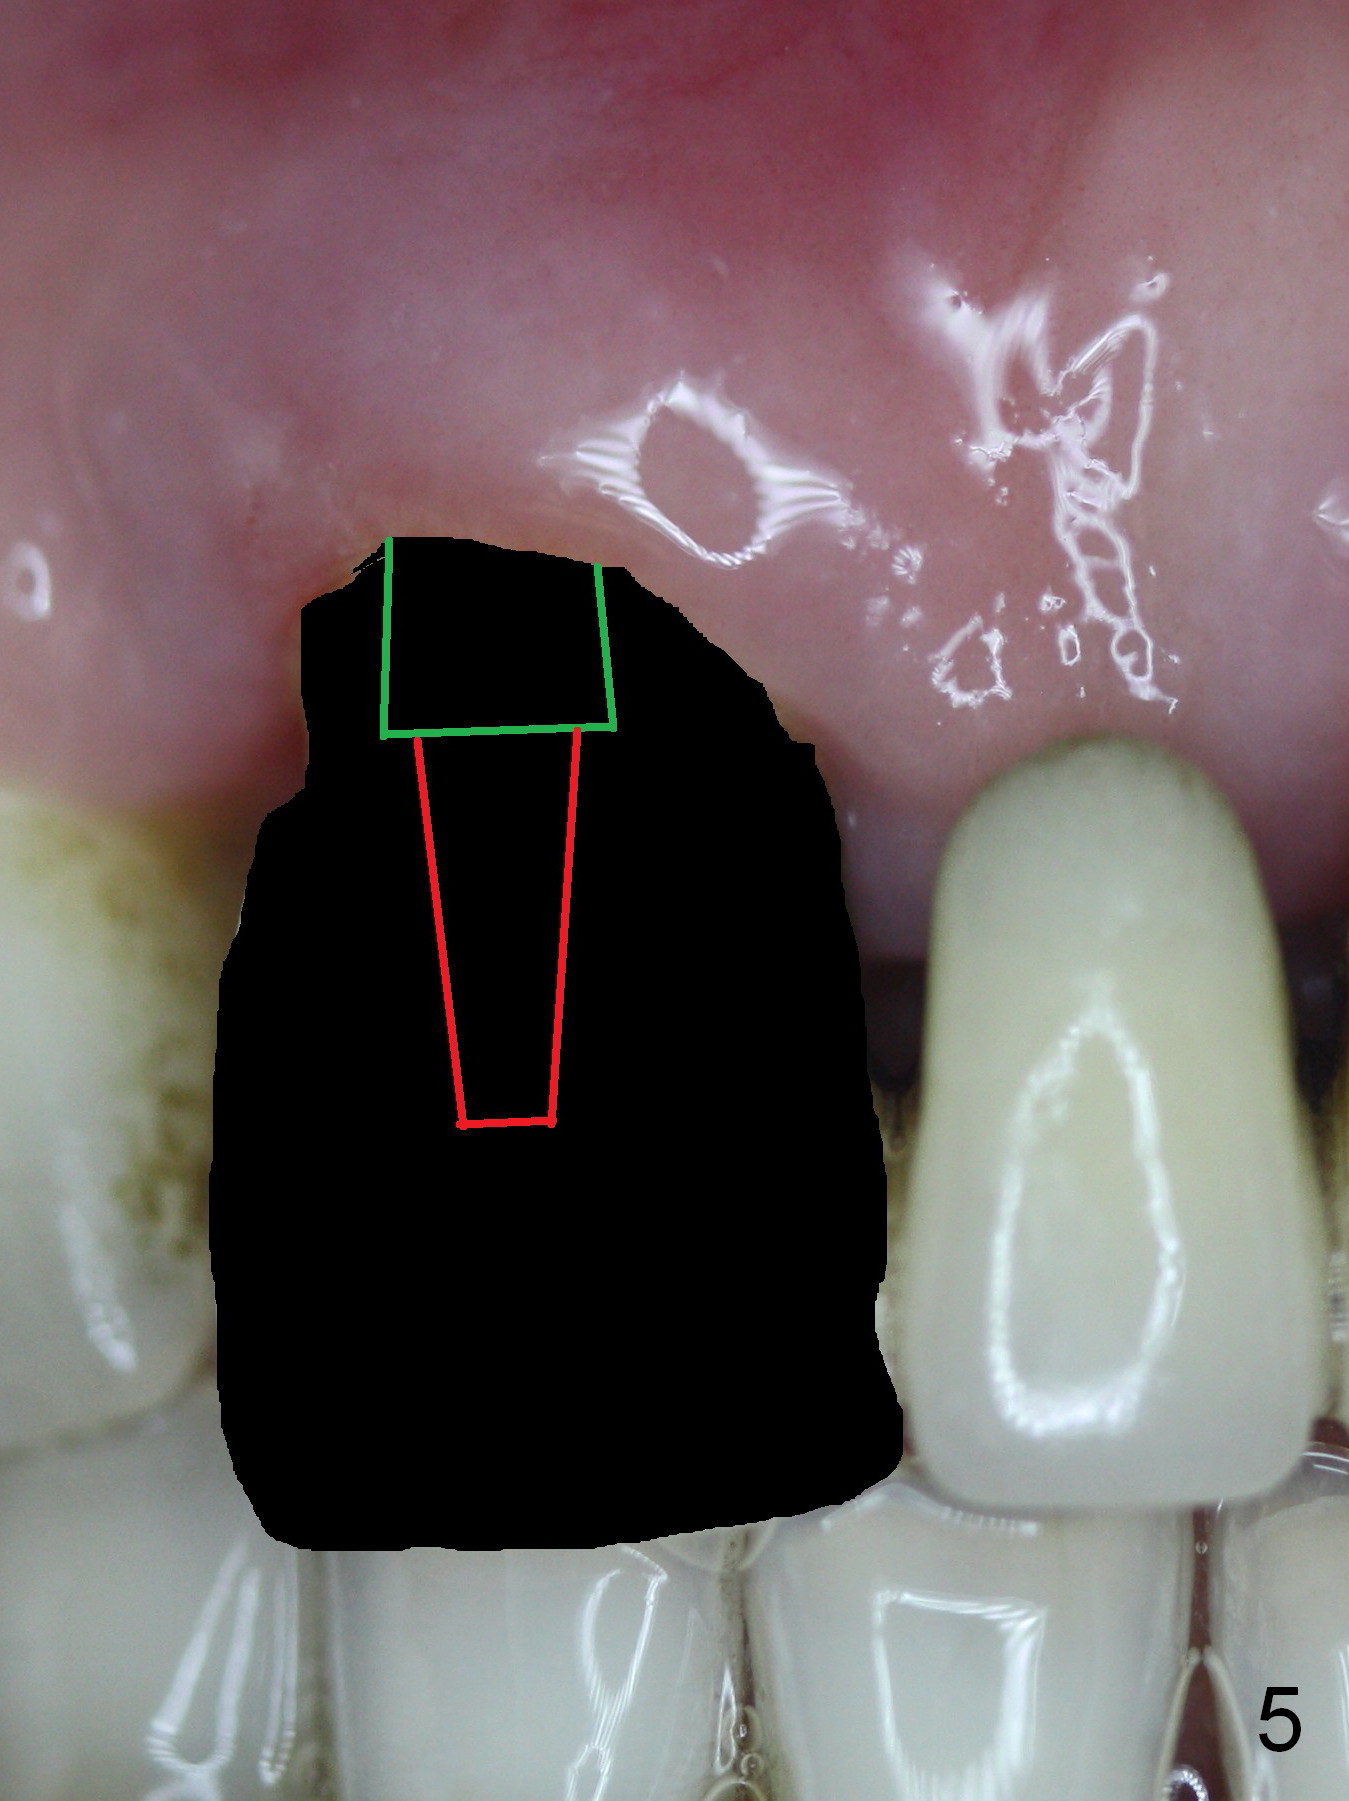

The 74-year-old patient is excited about having 3 implants placed without discomfort (1,2). He wants to take care of a loose FPD spanning from #8 to 9 (Fig.1). It appears that #8 is non-salvageable (Fig.2 * with deep pockets). There is severe bone loss around the affected tooth (Fig.3; Osteotape is expected for buccal and lingual defects). In addition, the Incisive Canal is abnormally large (arrowheads). The coronal end of a 4.5x20 mm implant and a 3.5x5 mm abutment will be slightly deviated mesially (Fig.4), since the 3-unit FPD will be converted to 2 single unit crowns. Surgical guide is ready. The 1st step is to section between #8 and the pontic (Fig.5; green outline: implant; red: abutment). If primary stability is low, the immediate provisional (Fig.8 white area) will be bonded the tooth #7 and the pontic as a supplementary measure (blue areas). Once the implant is osteointegrated, the distal portion of the pontic (Fig.7 *) will be removed. Acrylic is added to the mesial portion of the provisional (Fig.8 *) so that the papilla (P in Fig.7) will be pushed mesially and incisally (Fig.8 arrowheads). The step will be repeated a few weeks later (Fig.9). It could be done bilaterally at the same time by removing #9 crown and converting to the provisional. Finally the pontic will be removed. Two relatively wide crowns will be fabricated if the patient is satisfied with the provisional.